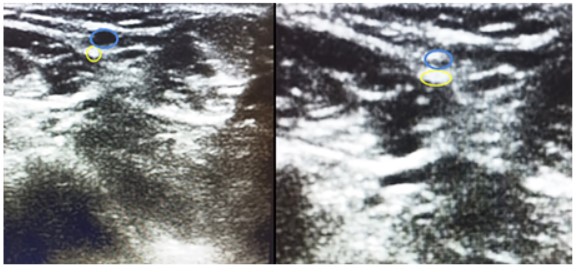

Se identifico el intervalo de la lesión en el tendón de Aquiles (Figura 2) y la trayectoria del nervio sural y su vena satélite (safena menor) mediante ecografía. Para identificar la vena fue de utilidad realizar compresión sobre los tejidos blandos y ver su colapso (Figura 3) (Figura 4).

Figura 3. Ecografía corte transversal al tendón: En la imagen de la izquierda se observa la vena safena menor (azul), en la imagen derecha se visualiza la misma al realizar compresión con el transductor.

Figura 4. Ecografía corte transversal al tendón: En azul se visualiza la vena safena menor sin compresión (izquierda) y con compresión derecha (en amarillo se identifica el nervio sural.